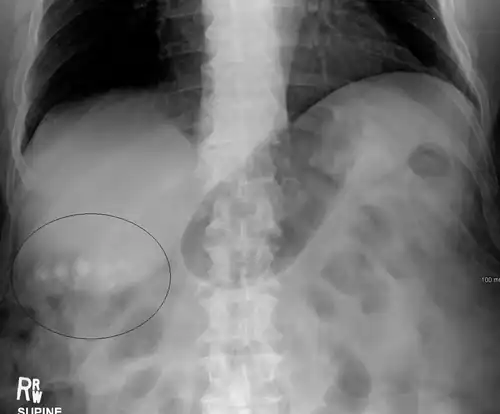

Large gallstones can potentially erode through the gallbladder wall and into the neighboring small intestine. This large stone then travels through the small intestine until it is too narrow for the stone to continue, causing a small bowel obstruction. This obstruction often occurs at previous surgical sites or at the ileocecal valve (the portion of the bowel where the small intestine meets the large intestine). The patient presents with the inability to defecate or pass gas, nausea, vomiting, and severe abdominal pain.[14]